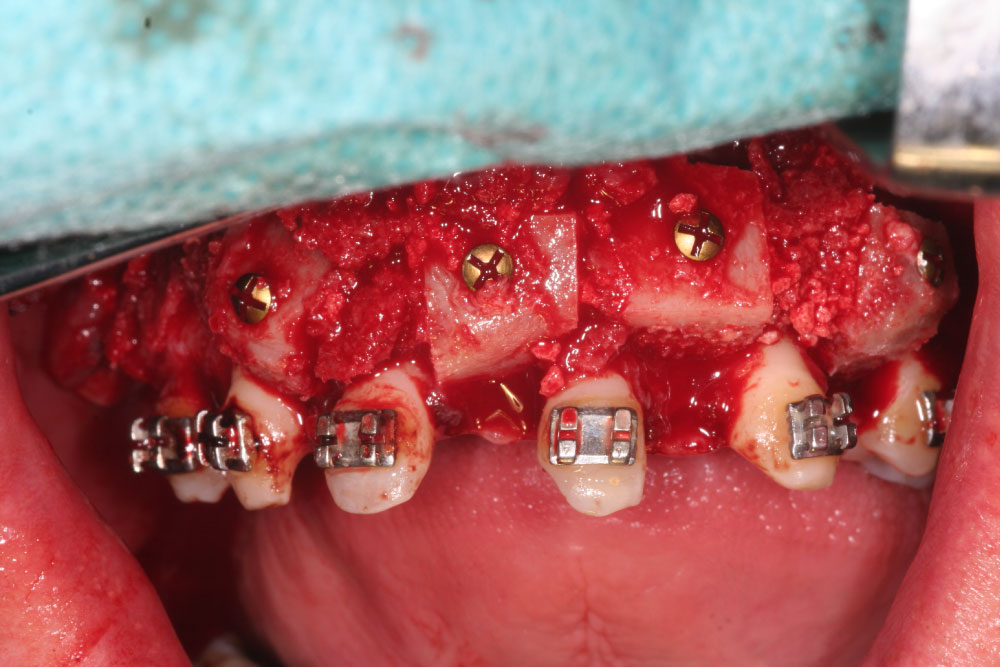

After 6 months of consolidation and ossification, the second surgical intervention was planned and performed as corrective osteotomy, beginning with the mandible. In course of the osteotomy according to Obwegeser/Dal Pont,the mandible was set back to the maxilla by splint for 8 mm, and fixed with one plate with cortical screws. After this, the maxilla was set forward by Le-Fort-I-Osteotomy for 12 mm and fixed, too. The first palatal widening 6 months ago turned out to be insufficient, so we decided to split the maxilla again along the sutura palatina mediana with activation for 8 mm. A second bone graft from the iliac crest was now used for alveolar augmentation in region 13-21 for a discontinuous palatal widening (Figure 6).

Figure 6: Maxillary osteotomy (LeFort I) and discontinuous palatal distraction; sagittal interpositioning of iliac crest graft. View Figure 6

In preparation for the planned implantations, gaps were needed in the maxilla as well as in the mandible. For this, we lateralized, medialized and distalized the corresponding teeth, so called orthodontic volume optimizing [47], (Figure 7a and Figure 7b). In the meantime, the cones of teeth 31/41 and 11/21 could be extracted during the time of 12 months. The plates for osteosynthesis could be removed and the alveolar ridge of maxilla and mandible was augmented with the iliac bone graft in regio 11-13, 23/24, 31/41, and 35 (Figure 8 and Figure 9). After that, we inserted implants in the maxilla in regio 16, 14, 12, 22, 11, 21, 24, and 26 and in the mandible in regio 36, 34, 31/41, 44, 46 (SI Cace, SIConepiece for teeth 14 + 34). Concerning the teeth 31/41, a bone split was set (Figure 10). The other teeth were pre-grinded as preparation for the later prosthetics of crowns and bridges. A model was prepared in the laboratory.

Figure 8: Secondary alveolar ridge augmentation with onlay-grafts from iliac crest. View Figure 8